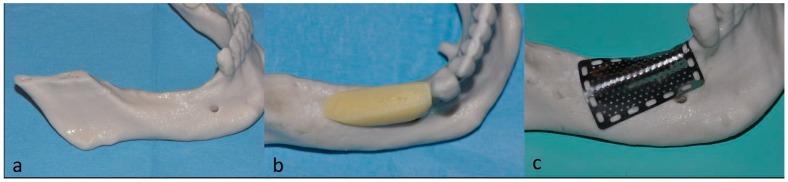

One of the most often used bone augmentation techniques is the guided bone regeneration procedure. The authors report the case of a 75-year-old man with an atrophic right posterior mandible who underwent bone augmentation through guided bone regeneration with a preshaped titanium mesh adapted on a stereolithographic model of the patient's jaw. The graft volume was simulated with a light-curing resin. The actual site was grafted with a mixture of autogenous and equine-derived bone. Five months later, the mesh was retrieved, three cylindrical implants were positioned, and a bone biopsy was collected for histomorphometric analysis. A provisional prosthesis was delivered three and a half months later. Definitive rehabilitation was accomplished after one additional month. The graft allowed for effective bone formation (newly formed bone, residual biomaterial, and medullar spaces were, respectively, 39%, 10%, and 51% of the core volume). The patient has functioned successfully throughout six and a half years of follow-up. Using the preshaped titanium mesh in association with the enzyme-treated equine bone substitute provided effective bone regeneration.

最常用的骨增量技术之一是引导骨再生术。作者报告了一例75岁男性患者,其右侧下颌骨萎缩,通过引导骨再生术进行骨增量,使用了根据患者颌骨的立体光刻模型定制的预成型钛网。用光固化树脂模拟移植骨体积。实际部位植入了自体骨和马源骨的混合物。五个月后,取出钛网,植入3枚圆柱形种植体,并采集骨活检样本进行组织形态计量学分析。三个半月后安装临时义齿。再过一个月完成最终修复。移植骨实现了有效的骨形成(新形成的骨、残余生物材料和骨髓腔分别占核心体积的39%、10%和51%)。在六年半的随访期间,患者功能良好。使用预成型钛网联合酶处理的马骨替代物可实现有效的骨再生。